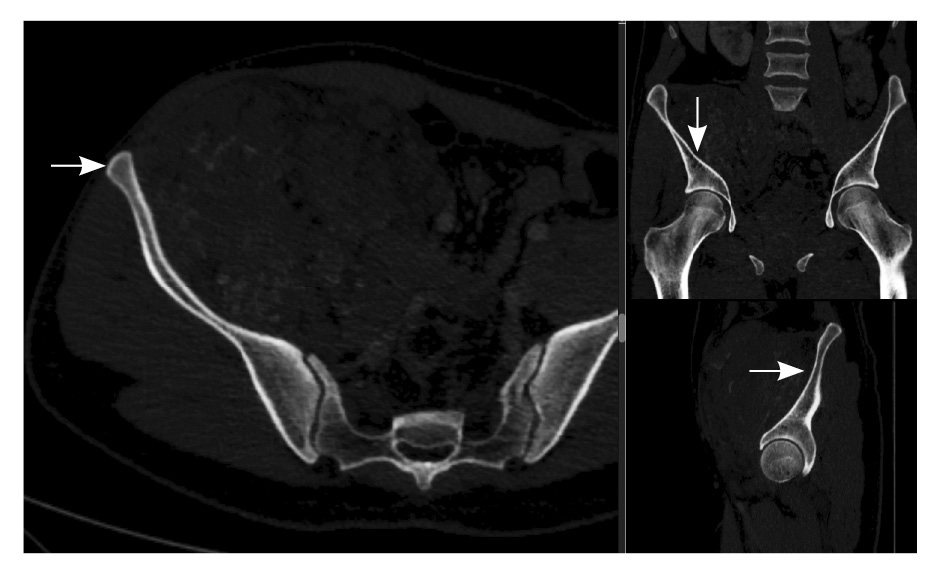

При контрольной томографии, проведенной на 5-е сутки после операции, забрюшинно справа определялась остаточная ткань опухоли размерами 125 × 81 × 90 мм. Резидуальный фрагмент прилегал к правой подвздошной кости, по ходу подвздошных сосудов, с распространением на переднюю поверхность правого бедра. Признаков экстравазации контрастного препарата не обнаружено (рис. 3).

Рис. 3. Мультиспиральная компьютерная томография органов брюшной полости и забрюшинного пространства с болюсным внутривенным контрастированием, венозная фаза. А – исследование до операции, Б – исследование после операции: резидуальный фрагмент образования (красная стрелка) тесно прилежит к подвздошной кости и подвздошным сосудам (головка синей стрелки)